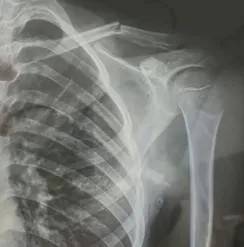

10月30日,内蒙古自治区赤峰市宁城县苏木皋小学一学生家长贾女士给记者打来电话,介绍了孩子被打的原因贵州茅台股票分析。贾女士称,放学通道的墙上有一个电灯的开关,好多孩子放学时都随手去拨弄开关。出于安全考虑,学校和老师都禁止孩子拨弄开关。23日放学时,他儿子和另一个同学调皮,再去拨弄了那个开关,被正在值班的另一个班的班主任发现,把她儿子打了,且打骨折了。

图片由报料者提供